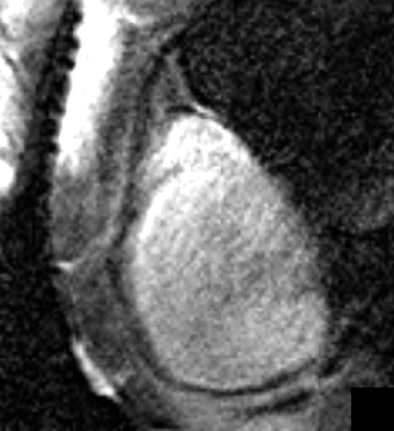

| Reformatted right coronary artery vessel wall images of a healthy 24-year-old man acquired with Cartesian k-space imaging (above) and radial k-space imaging (below). Image republished with permission of the American Society of Roentgenology ©, from AJR 2007; 188:70-74. Paul M. Bansmann, Andrew N. Priest, Kai Muellerleile, Alexander Stork, Gunnar K. Lund, Michael G. Kaul, and Gerhard Adam. |